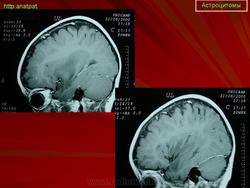

ГМ. Астроцитома. +

Астроцитома.